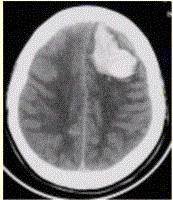

问题 患者男,45岁,突发剧烈头痛伴呕吐30min。既往有高血压病史,平日血压为(190~160)/(100~110)mmHg。查体:右侧肢体肌力Ⅱ级,无颈项强直。CT表现如下图。 以急性脑卒中起病的患者,应首选的影像学方法是

选项 A.CT B.MRI C.X线平片 D.B超 E.放射性核素

答案 A